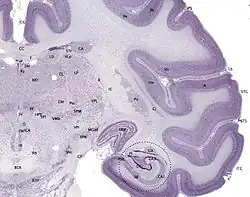

brainmaps.org, CC-BY-SA 3.0

The hippocampus can be seen as a ridge of gray matter tissue, elevating from the floor of each lateral ventricle in the region of the inferior or temporal horn.[12][13] This ridge can also be seen as an inward fold of the archicortex into the medial temporal lobe.[14] The hippocampus can only be seen in dissections as it is concealed by the parahippocampal gyrus.[14][15] The cortex thins from six layers to the three or four layers that make up the hippocampus.[16]

The hippocampus, including the dentate gyrus, has the shape of a curved tube, which has been compared to a seahorse, and a ram's horn (Cornu Ammonis). Its abbreviation CA is used in naming the hippocampal subfields: CA1, CA2, CA3, and CA4.[15] It can be distinguished as an area where the cortex narrows into a single layer of densely packed pyramidal neurons, which curl into a tight U shape. One edge of the "U," – CA4, is embedded into the backward-facing, flexed dentate gyrus. The hippocampus is described as having an anterior and posterior part (in primates) or a ventral and dorsal part in other animals. Both parts are of similar composition but belong to different neural circuits.[17] In the rat, the two hippocampi resemble a pair of bananas, joined at the stems by the commissure of fornix (also called the hippocampal commissure). In primates, the part of the hippocampus at the bottom, near the base of the temporal lobe, is much broader than the part at the top. This means that in cross-section the hippocampus can show a number of different shapes, depending on the angle and location of the cut.

In cross-section of the hipppocampus, including the dentate gyrus, several layers will be shown. The dentate gyrus has three layers of cells (or four if the hilus is included). The layers are from the outer in - the molecular layer, the inner molecular layer, the granular layer, and the hilus. The CA3 in the hippocampus proper has the following cell layers known as strata: lacunosum-moleculare, radiatum, lucidum, pyramidal, and oriens. CA2 and CA1 also have four each of these layers and not the lucidum stratum.